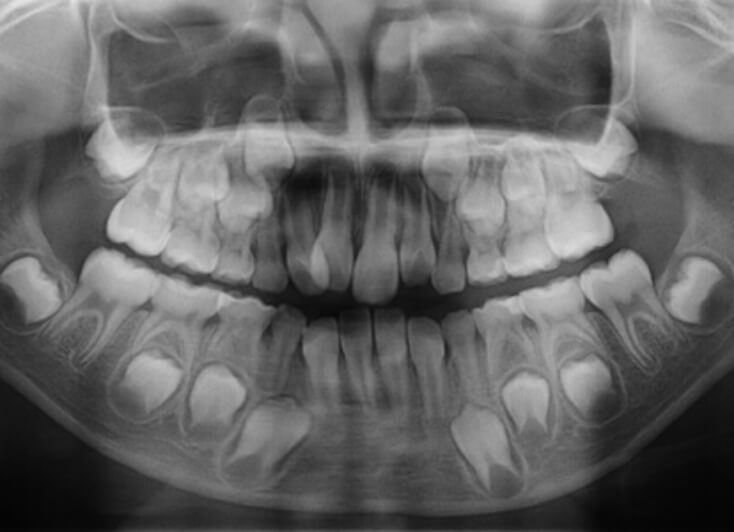

- STEP.02

- 資料採取

治療のための必要な情報を収集していきます。CT撮影・口腔内を診察し、虫歯などが無いか確認します。

- STEP.03

- 治療計画

資料採取の結果から矯正治療に適しているか、ご希望の治療方法が可能か等の診断結果をご説明します。 資料採取の結果をもとに矯正の治療方法、治療期間や治療費用についてご提示して矯正治療の計画をお話しします。